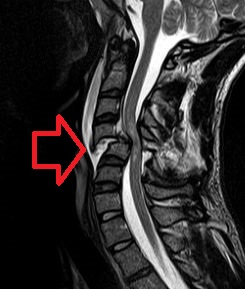

Parallelamente, è essenziale confermare la presenza, la sede e l’entità della lesione midollare attraverso indagini radiologiche mirate, quali radiografia (RX), tomografia computerizzata (TC) e risonanza magnetica (RM) della colonna vertebrale.